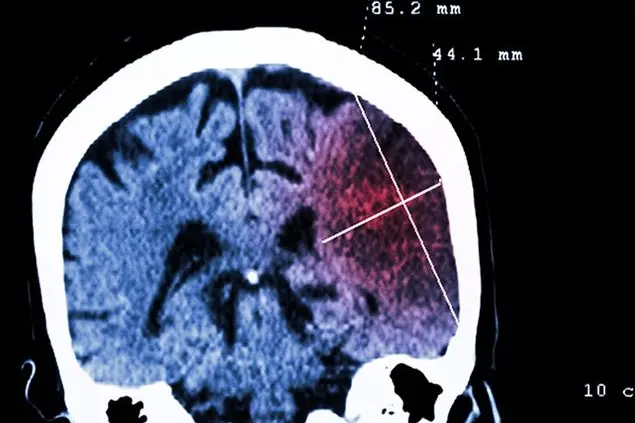

Seppure la mortalità sia diminuita nell’ultimo decennio, oggi l’ictus è fatale per una persona su cinque. Purtroppo però, nel nostro Paese è la prima causa di invalidità con conseguenze, anche gravi: tre pazienti su quattro, infatti, convivono con qualche forma di disabilità, la metà non è più autosufficiente. Il professor Vincenzo Di Lazzaro, docente di Neurologia all’Università Campus Biomedico di Roma, ospite della trasmissione Il mio medico su Tv2000, ci spiega perché ogni minuto fa la differenza per evitare gravi conseguenze.